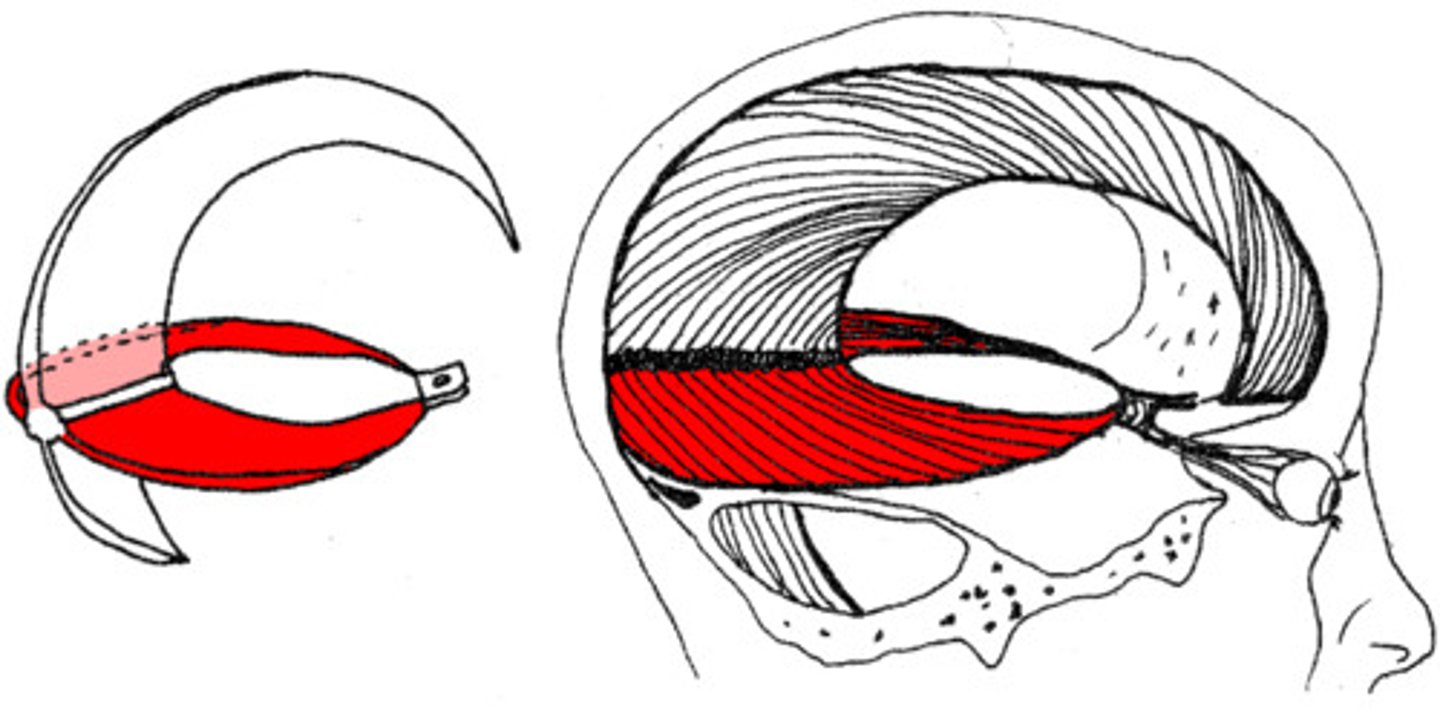

corpus callosum

the large band of neural fibers connecting the two brain hemispheres and carrying messages between them